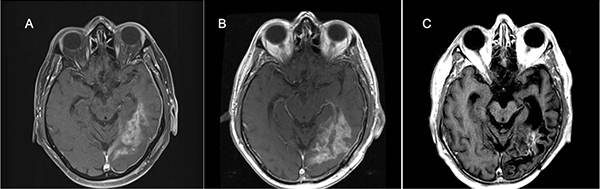

Figure 2: 64-year-old man with IDH wild-type and MGMT promoter unmethylated GBM, treated with selinexor on Arm D, given as third-line after progression of disease despite radiotherapy and temozolomide (first-line) and experimental AKT inhibitor combined with mTOR inhibitor (second-line).

Magnetic resonance contrast-enhanced axial T1 images taken throughout the course of treatment are shown after subtotal resection of recurrent GBM (A), and further increase in tumor size ~3 weeks after the post-operative MRI as a new baseline (B), the patient received selinexor on Arm D, and a durable partial response (C) was observed beginning ~73 weeks after starting selinexor with a maximum tumor size reduction of 72 percent. At the time of data lock, treatment of this patient continued through Karyopharm's Expanded Access Program (KEAP), and he remained in a partial response after 42 months of selinexor when data collection ceased.